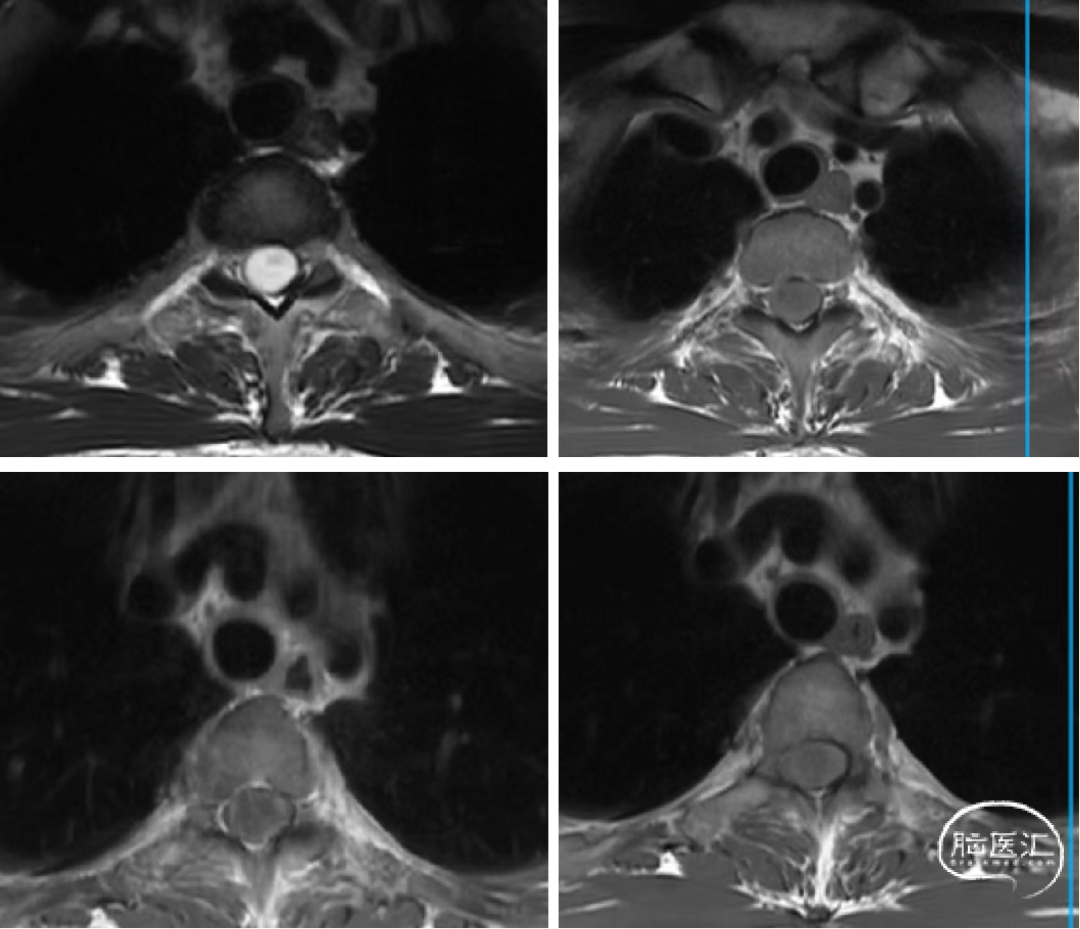

术前胸椎MR如下:

T1-6髓内病灶:室管膜瘤?